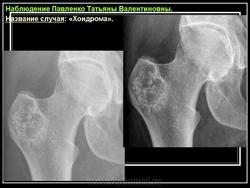

Рентгенологическая картина хондромы представляет четко очерченный опухолевый узел. Очаги минерализации в хондромах выглядят достаточно характерно и представлены очаговыми, глыбчатыми или кольцевидными , арочными отложениями извести. Полного разрушения кортикального слоя трубчатой кости с выходом опухолевых масс в мягкие ткани не наблюдается.